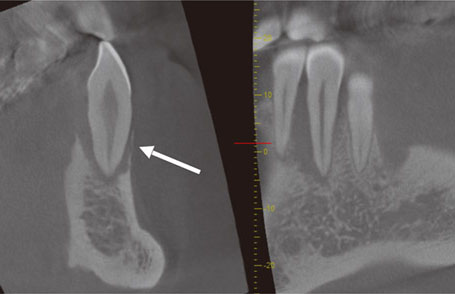

特に、歯根の観察においては、横断像(Z断面)において3断面の交点を歯根の中心(即ち根管)に置き、画面をドラッグしながら微小な回転を行い、断面方向が歯根の頰舌方向、または近遠心方向に一致するように調整すると、他の断面上で歯根の縦方向の断面像が鮮明に表れます(図20、21)。

図20 #37の根管を表示しようとしたが、横断像(左側)において断面の方向(直行した2直線)は歯根断面で斜め方向になっており、歯列平行断像(右側)では根管はうまく表示できていない。

図21 断面方向を歯根断面にそれぞれ垂直方向に調整すると(左側)、根管が鮮明に表示できた(右側)。